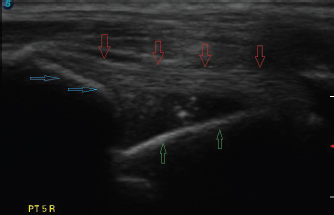

Fig. 3. Longitudinal ultrasound image of an intact biceps tendon (red arrows), supraglenoid tubercle (blue arrows), and proximal humerus (green arrows).

The dog was placed in lateral recumbency with the affected limb uppermost. Hair was clipped to expose the humeral tubercle and intertubercular groove. Using a 12 mHz linear probe, the biceps tendon was visualized longitudinally from the musculotendinous junction within the groove, proximally to the tendinous origin on the supraglenoid tubercle (Fig. 3). Any abnormalities and the approximate tendon size were noted. The biceps tendon was then positioned under tension by placing the shoulder in flexion with concurrent elbow extension, so that the forelimb lay roughly parallel to the topline. With the limb in this position, the appearance of the biceps tendon as it spanned the glenohumeral joint was noted, and images were saved to the ultrasound’s hard drive.